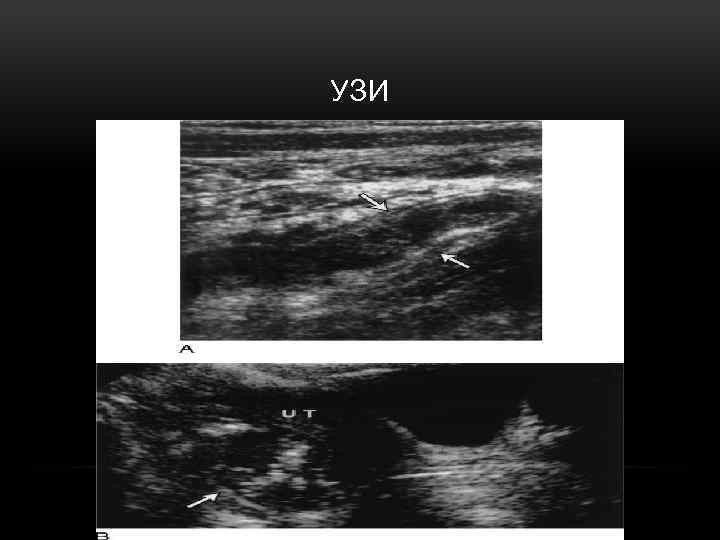

ИНСТРУМЕНТАЛЬНЫЕ ИССЛЕДОВАНИЯ • Рентгенография ОБП • УЗИ • КТ • Лапароскопия Эти методы используются в сомнительных случаях, в том числе – для дифференциальной диагностики и исключения других заболеваний, симулирующих острый аппендицит

УЗИ